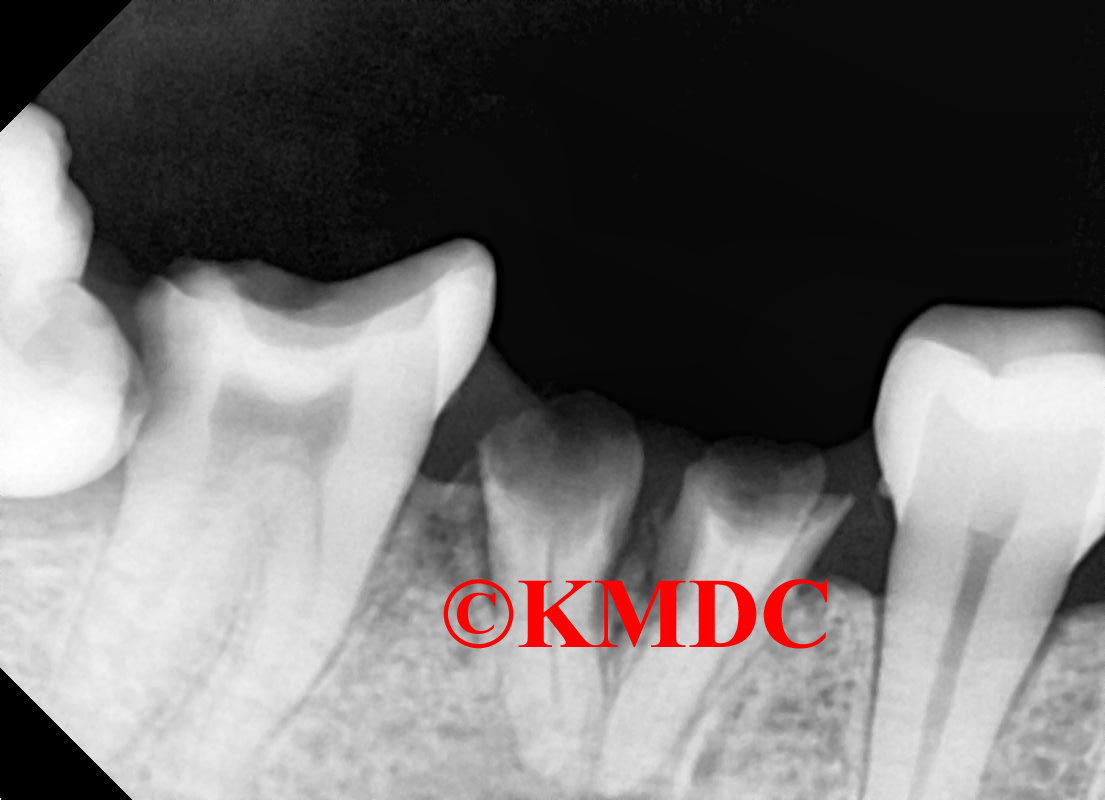

Clinical Gallery